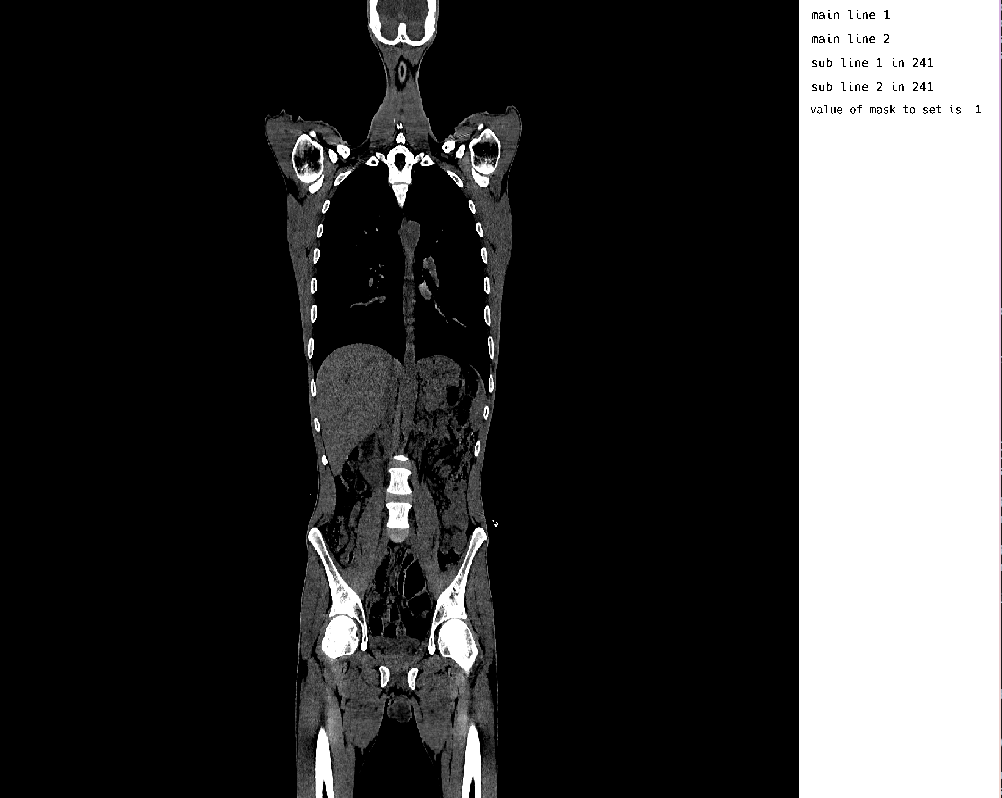

MedEye3d.DisplayDataManag.setDisplayedData(medEyeStruct, displayData)The result of this Gaussian noise within the annotation layer, made for an outcome like the following: